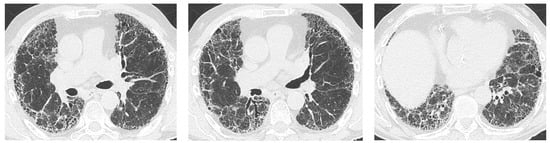

4.1. How Does Radiologic/Histopathologic Pattern Influence the Clinical Picture and Management of pSS-ILD Patients? What Is the Role of Lung Biopsy?

- Egashira, R.; Kondo, T.; Hirai, T.; Kamochi, N.; Yakushiji, M.; Yamasaki, F.; Irie, H. CT Findings of Thoracic Manifestations of Primary Sjögren Syndrome: Radiologic-Pathologic Correlation. Radiographics 2013, 33, 1933–1949. [Google Scholar] [CrossRef] [PubMed]

- Dong, X.; Zhou, J.; Guo, X.; Li, Y.; Xu, Y.; Fu, Q.; Lu, Y.; Zheng, Y. A retrospective analysis of distinguishing features of chest HRCT and clinical manifestation in primary Sjögren’s syndrome-related interstitial lung disease in a Chinese population. Clin. Rheumatol. 2018, 37, 2981–2988. [Google Scholar] [CrossRef]

- Kamiya, Y.; Fujisawa, T.; Kono, M.; Nakamura, H.; Yokomura, K.; Koshimizu, N.; Toyoshima, M.; Imokawa, S.; Sumikawa, H.; Johkoh, T.; et al. Prognostic factors for primary Sjögren’s syndrome-associated interstitial lung diseases. Respir Med. 2019, 159, 105811. [Google Scholar] [CrossRef]

- Enomoto, Y.; Takemura, T.; Hagiwara, E.; Iwasawa, T.; Fukuda, Y.; Yanagawa, N.; Sakai, F.; Baba, T.; Nagaoka, S.; Ogura, T. Prognostic Factors in Interstitial Lung Disease Associated with Primary Sjögren’s Syndrome: A Retrospective Analysis of 33 Pathologically–Proven Cases. PLoS ONE 2013, 8, e73774. [Google Scholar] [CrossRef] [PubMed]

- Ito, I.; Nagai, S.; Kitaichi, M.; Nicholson, A.G.; Johkoh, T.; Noma, S.; Kim, D.S.; Handa, T.; Izumi, T.; Mishima, M. Pulmonary manifestations of primary Sjogren’s syndrome: A clinical, radiologic, and pathologic study. Am. J. Respir. Crit. Care Med. 2005, 171, 632–638. [Google Scholar] [CrossRef]

- Enomoto, Y.; Takemura, T.; Hagiwara, E.; Iwasawa, T.; Okudela, K.; Yanagawa, N.; Baba, T.; Sakai, F.; Fukuda, Y.; Nagaoka, S.; et al. Features of usual interstitial pneumonia in patients with primary Sjögren’s syndrome compared with idiopathic pulmonary fibrosis. Respir. Investig. 2014, 52, 227–235. [Google Scholar] [CrossRef] [PubMed]